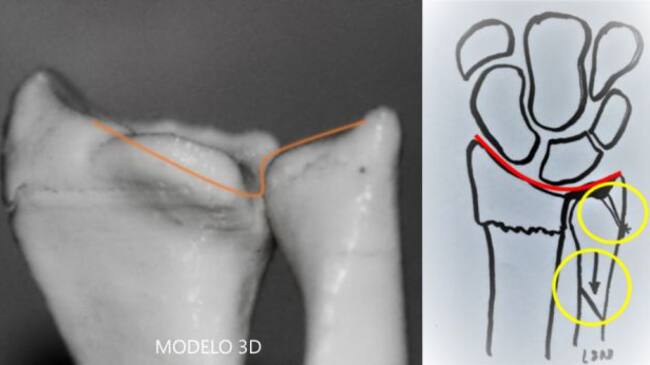

Para crear el modelo 3D de la zona que se va a intervenir primero realizan una tomografía computerizada al paciente, lo que conocemos como TAC, o un resonancia magnética (RM), son imágenes en dos dimensiones, con superposición de las estructuras. La realización de un modelo impreso en 3D requiere de un potente equipo informático, capaz de transformar las imágenes de un TAC o una RM en una reconstrucción en tres dimensiones, la cual es transmitida a una impresora, que, utilizando un material específico, transforma esa información en un objeto físico, reproducción exacta de la anatomía del paciente individualizado.

Esta réplica del hueso se entrega a los cirujanos para que puedan ver de un modo real lo que se van a encontrar en la intervención y, así poder planificar la cirugía, elaborar líneas de corte (elegir y modelar los implantes a usar, sean prótesis, placas de osteosíntesis, etc.) y aplicarlas sobre la pieza. Esto permite realizar resecciones con una precisión milimétrica en un espacio que es muy complicado de ver durante la intervención, según el doctor Luis Sánchez Navas, jefe de Traumatología de Quirónsalud Alicante, “esta réplica personalizada reduce mucho el margen de error, disminuye el tiempo quirúrgico y por tanto, las complicaciones derivadas de una larga exposición mejora el porcentaje de éxito de la intervención y la recuperación del paciente porque, al planificar con antelación la forma de la cirugía, consiguen que la intervención se haga en menos tiempo y de un modo más limpio”.

Mediante la impresión de un modelo 3D se pudo valorar la lesión, decidir el tratamiento más adecuado (un acortamiento del cúbito y una reinserción del menisco mediante artroscopia) y planificar todo el procedimiento.